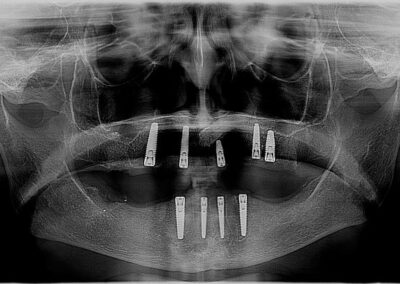

This is a wonderful case of a patient who had broken teeth for a very long time. The outcome is a supported set of full dentures on implants. The patient does not experience movement of teeth and has the ability to eat all food. The implant supported denture allows the patient to have a very high biting force, which is very important when you want to eat crunchy fresh fruits and vegetables. This was a fully guided case.